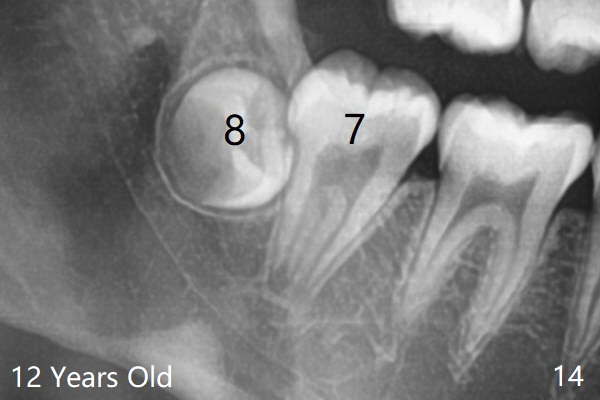

Posterior panoramic X-ray taken immediately pre banding shows impaction of LL7,  blocked by LL8 (Fig.14).   There appear to be a cyst and a tunnel coronal to LL7 (Fig.14 *, T).   CT is mandatory.

The tooth bud of LL8 appears to be close to that of LL7 at the age of 7.5 years (Fig.5).病人7岁时左下智齿牙胚好像已经接近7(图五与右侧比较)。现在左下七冠方仿佛有牙囊(图十四*)和隧道(T)。拔除智齿时,七牙合面骨质应该去除。术前将拍摄CT。